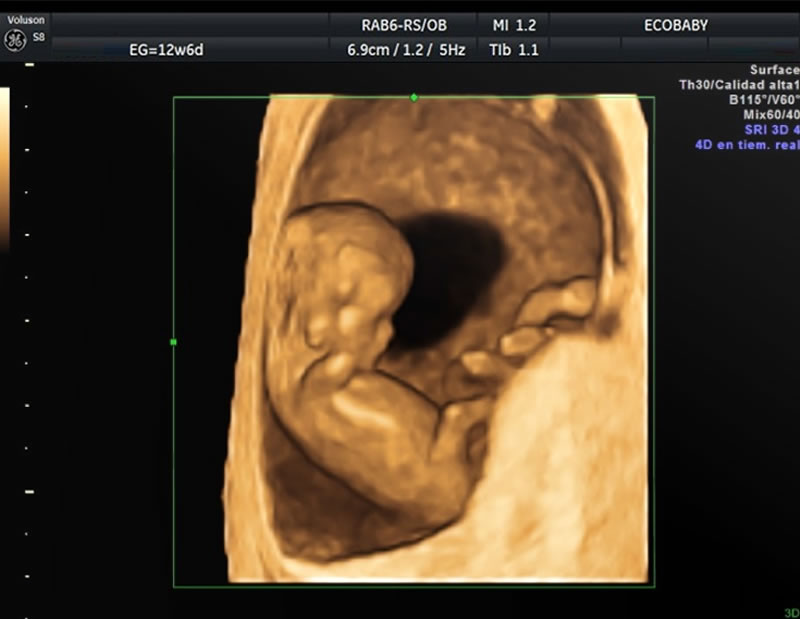

En el Primer Trimestre del Embarazo

Esta ecografía se utiliza para determinar la correcta ubicación del embrión dentro de la cavidad uterina, determinar la edad gestacional (tiempo de embarazo) y la vitalidad del mismo (latidos), así como el número de embriones.